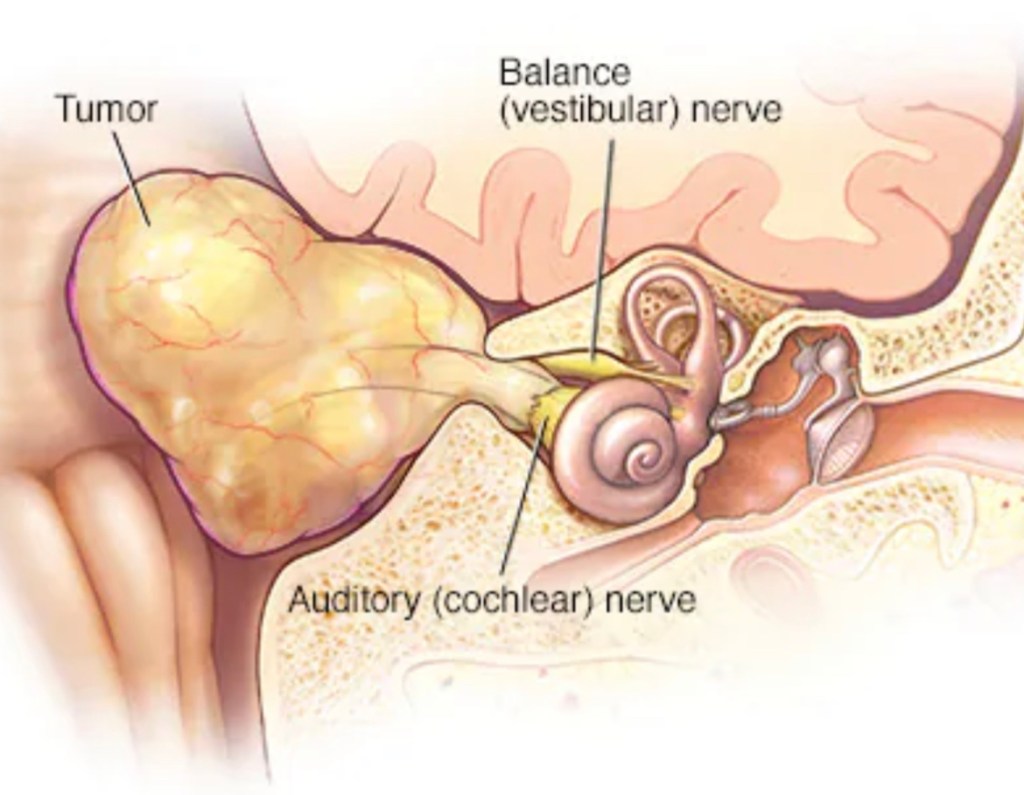

So now I have something called an acoustic neuroma – which is fancy for a non-cancerous tumor. Acoustic Neuroma info

WHEN? When is your surgery? That has been the big question. I have to get a CT scan on Monday and then hopefully we’ll be able to kick this tumor out. She’s gotten quite comfortable in there, which makes the surgery pretty involved. They can’t preserve my hearing, but they have to be careful around those other nerves.

We will try to keep everyone updated the best we can – the good, the hard and the ugly. I’m gonna have a rocking new haircut involving a shaved side by my right ear. I’m also going to be in the hospital for about 4 days. Then it is recovery and physical therapy time. This thing has damaged my hearing in the one ear permanently and there’s a good chance it will temporarily affect my vestibular nerve – leaving me quite dizzy.